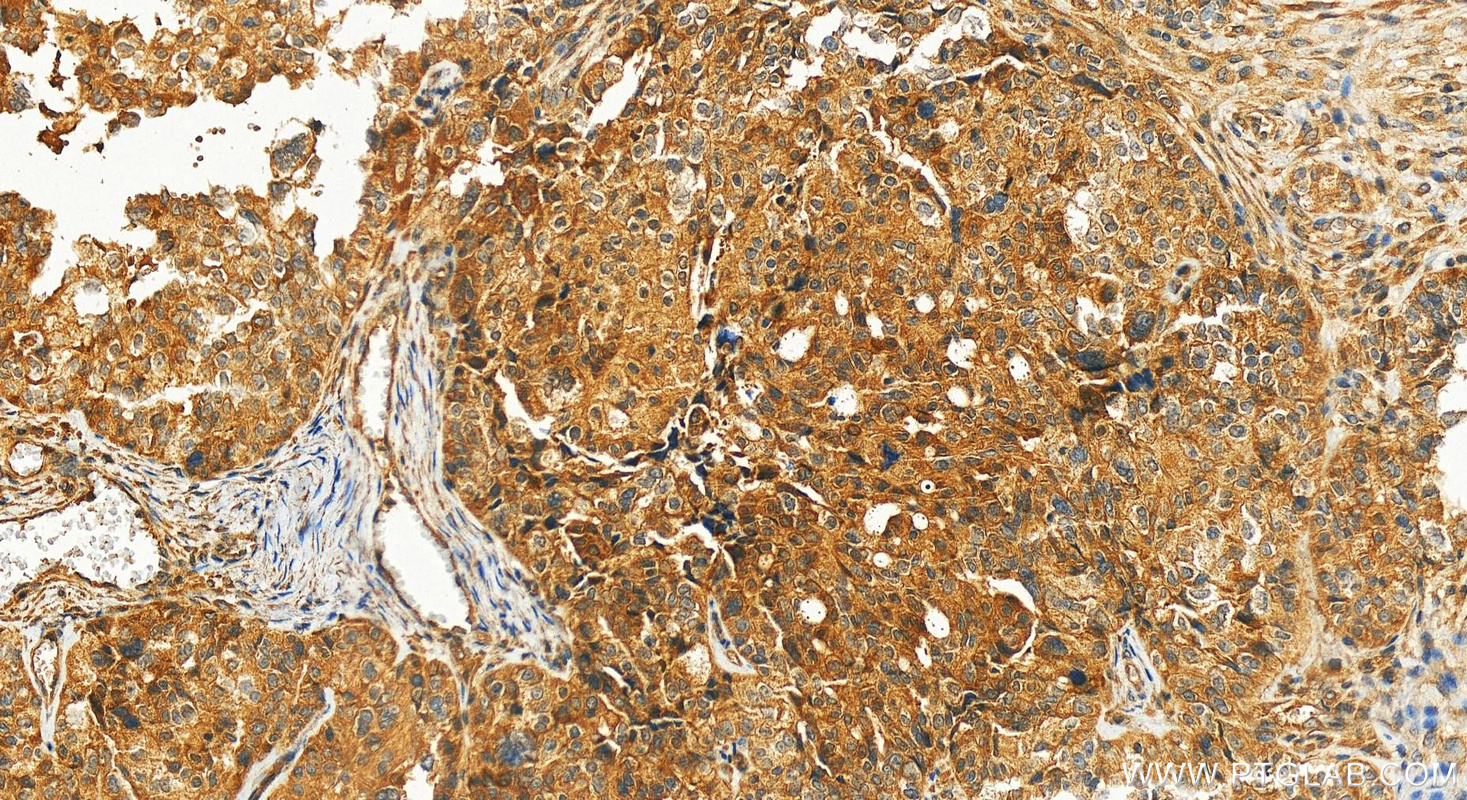

| Positive IHC detected in | human ovary cancer tissue Note: suggested antigen retrieval with TE buffer pH 9.0; (*) Alternatively, antigen retrieval may be performed with citrate buffer pH 6.0 |

| Immunohistochemistry (IHC) | IHC : 1:250-1:1000 |